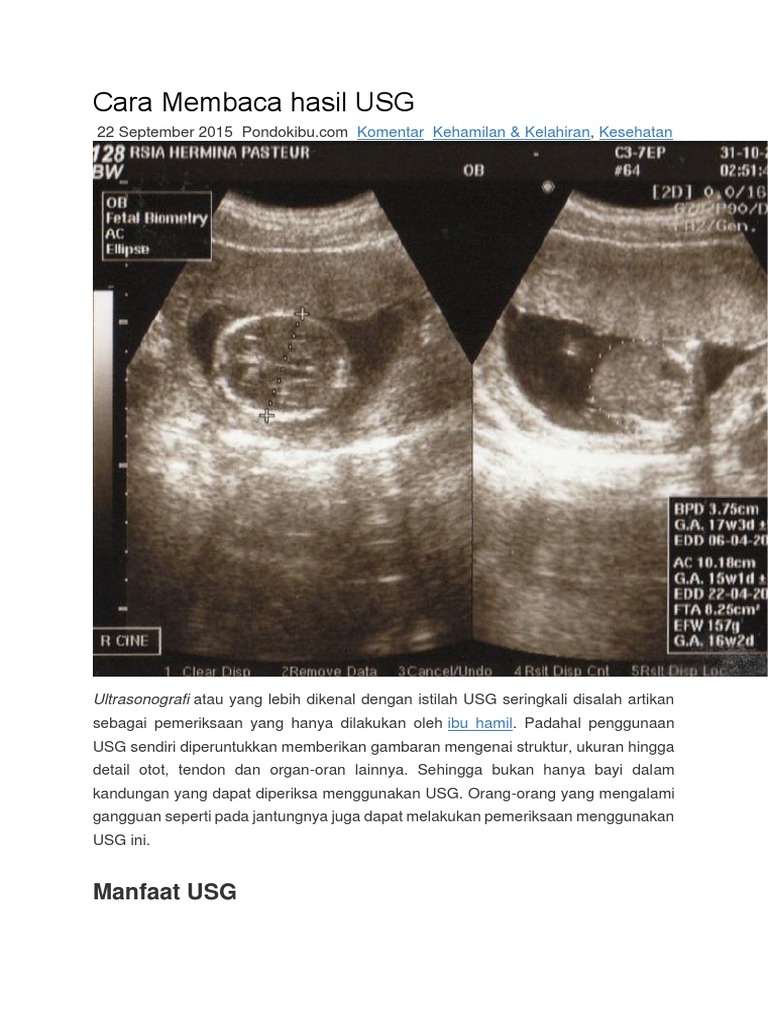

Cara Membaca Hasil Usg Docx